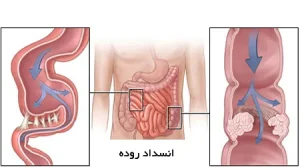

انسداد روده چیست و چرا میتواند کشنده باشد؟

انسداد روده، که در پزشکی به آن ایلئوس گفته میشود، وضعیتی موقت است که در آن رودهها قادر به عبور غذا و مواد زائد از بدن نیستند. رودهها لولههای طولانی و پیچخوردهای در داخل شکم هستند که معده را به مقعد متصل میکنند و به دو بخش اصلی تقسیم میشوند: روده کوچک و روده بزرگ.

روده کوچک وظیفه تجزیه و جذب مواد مغذی غذا را بر عهده دارد، در حالی که روده بزرگ با جذب آب و حرکات موجمانند، مواد هضم شده و زائد را به سمت مقعد هدایت میکند تا دفع شوند. ایلئوس زمانی رخ میدهد که این حرکات موجی موقتی متوقف شوند و معمولاً بین یک تا سه روز ادامه پیدا میکند.

این اختلال میتواند ناشی از عوامل مختلف و شرایط زمینهای باشد که باعث انسداد روده میشوند. انسداد میتواند بخشی از روده را درگیر کند (انسداد جزئی) یا کل طول روده تحت تأثیر قرار گیرد، که شدت علائم و ضرورت اقدامات درمانی را تعیین میکند.